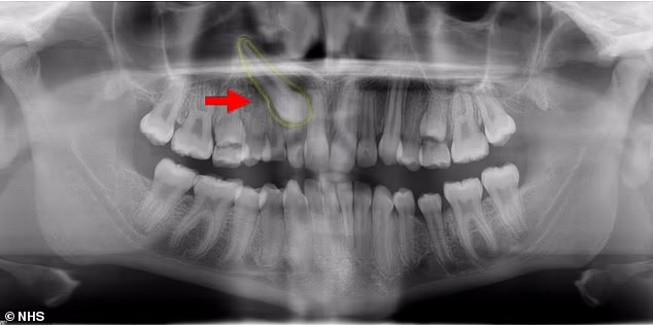

Врачи провели мужчине риноскопию и нашли в одной из ноздрей плотную белую массу, которая не вызывала болевых ощущений. Оказалось, что это эктопический зуб длиной 14 миллиметров, который вырос не там, где ему следовало бы.

Мужчине провели операцию и удалили зуб, вскоре проблемы с дыханием прекратились.